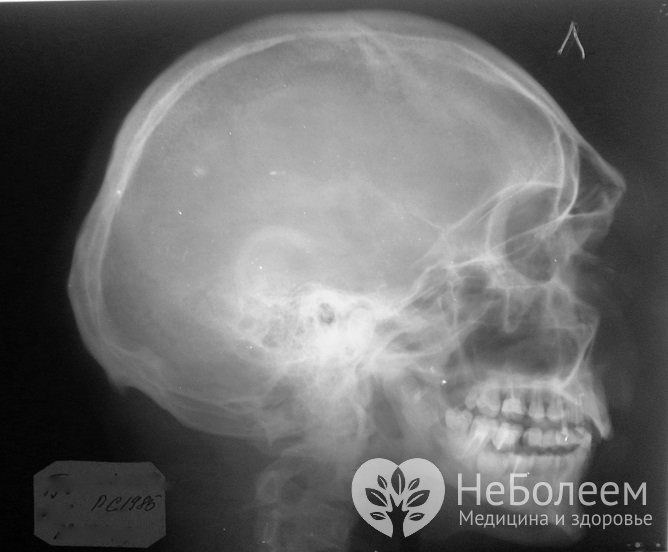

Для уточнения диагноза может потребоваться проведение рентгенографииПри проведении оценки общего состояния необходимо определить неврологический статус и объем кровопотери. Для исключения перелома либо определения его локализации проводится рентгенография костей органа в боковой и, возможно, прямой проекции.

У детей младшего возраста трактовка данных рентгенологического исследования затруднена, поскольку лицевые кости у них тонкие, обызвествлены не до конца и дают слабовыраженную рентгеноконтрастную тень, на которую происходит наслаивание интенсивной тени зубных зачатков и зубов.

При закрытой травме диагностика усложняется отеком тканей. При необходимости уточнения диагноза может потребоваться проведение КТ (компьютерной томографии) костей и придаточных пазух носа.